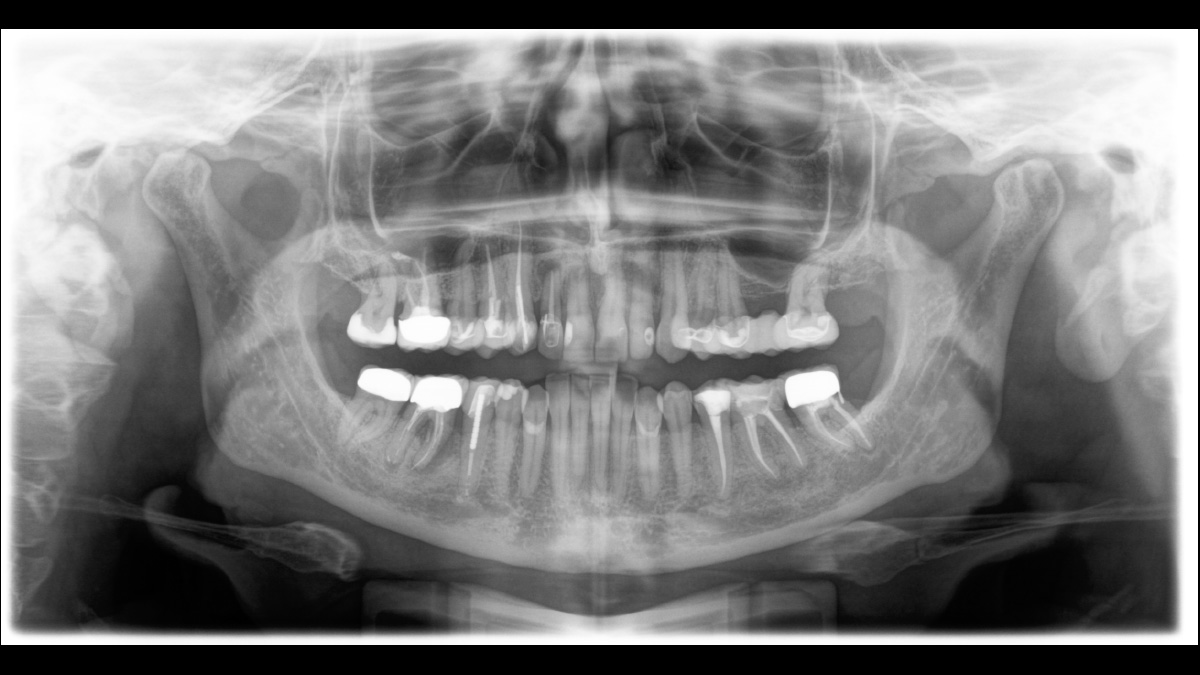

El equipo de radiología 2D/3D de alta calidad con una amplia gama de servicios para cada clínica. Ya sea como un dispositivo puramente 2D o como un módulo 3D, el Orthophos S es un socio confiable y está optimizado para las tareas diarias. Su sensor CsI Plus con función de autofoco garantiza imágenes claras, incluso en casos anatómicamente difíciles. El posicionamiento automático del paciente junto con el bloque de mordida oclusal patentado permite un posicionamiento del paciente fácil y que ahorra tiempo. Para su uso en ortodoncia, la Orthophos S también está disponible con un brazo cefalométrico opcional. Y como para Dentsply Sirona es importante estar preparado para el futuro, el brazo cefalométrico se puede reacondicionar en cualquier momento.

Incluso en casos anatómicamente difíciles con el sensor 2D CsI con función de autofoco

El enfoque correcto es crucial para excelentes radiografías panorámicas. Con la función de autofoco, usted recibirá automáticamente una imagen con la mejor nitidez posible en foco. Los dispositivos de radiología de Dentsply Sirona toman varios miles de imágenes individuales en un ciclo e identifican automáticamente las áreas donde la mandíbula está posicionada de manera óptima. Luego, sin ningún paso manual adicional, estas imágenes se muestran en una nítida imagen final.

Solo algunas partes de la imagen están en foco, mientras que otras áreas están borrosas.

El sistema detecta las áreas relevantes a partir de varios miles de imágenes individuales en un ciclo e identifica automáticamente las áreas donde la mandíbula está posicionada de manera óptima.

Imágenes nítidas.